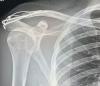

Utrhnul jsem si vazy v rameni dominantní ruky po pádu přes řidítka, původně diagnostikováno na Tossy II. – III., po kontrolním rentgenu jasná Tossy III. určenná k operaci.

- doporučuju si ofotit nebo vyžádat rentgenové snímky, já zatím fotil monitory, co mi doktoři ukázali, ale prej to dávaj i na jiná média typu CéDéčko a tak (v čem to v dnešní době přehraješ, to je už druhá otázka :-)

- pokud půjdete na operaci, nedoufejte v nějakou laparoskopii, je potřeba pečlivě prozkoumat co a kde se utrhnulo, na rentgenu to nidko přesně nepozná a vidět jsou jen kosti jak nejsou tam, kde mají být (ostatně jizvy z „boje“ prej chlapa ctí)